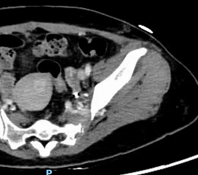

患者盆腔出血病情稳定一周后,经严格控制血压、稳定心率、卧床制动等治疗后,复查主动脉CTA提示主动脉夹层较前有所进展。主动脉疾病MDT团队——包括心血管外科、介入医学科、麻醉科、重症医学科(因患者合并骨盆骨折、血尿,还邀请了肾内科、泌尿外科、四肢关节骨科)等多学科专家进行了深入讨论,考虑该患者Stanford B型主动脉夹层累及范围广泛,如同体内“不定时炸弹”,具有限期手术干预指征,需要及时精确拆除。

△注:主动脉内膜呈螺旋形撕裂,夹层形成,随时可能因主动脉破裂、脏器缺血坏死等而危及生命。